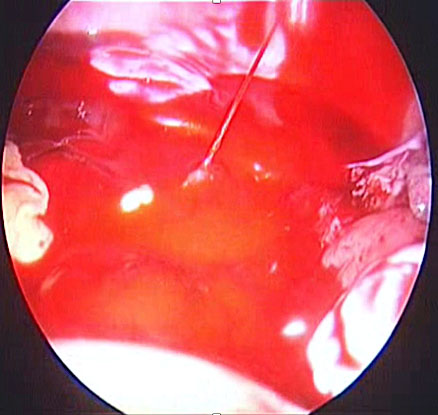

In the event of uterine artery bleeding during dissection, once identified, the laparoscopist should remain calm. CO₂ insufflation and suction at pressures below 300 mmHg help maintain pneumoperitoneum. The bleeding vessel should be carefully grasped with bipolar cautery forceps or another appropriate instrument (Figure 17) after adequate dissection. Occasionally, the presence of a gauze piece can help localize the bleeding source. It is important to avoid forcefully grasping the bleeding area, as the uterine artery lies above the ureter, which in turn is above the uterine vein. If the bleeding originates from the vein, bipolar cautery may inadvertently damage the ureter. Once hemostasis is achieved, hemostatic agents such as Surgicel may be applied, although they are often unnecessary.

(a) |

(b) |

(c) |

17

(a) Right uterine artery active bleeding after removal of the uterus. (b) Stabilizing the bleeder by atraumatic forceps with suction. (c) Stabilized tip of the vessel coagulated with bipolar cautery forceps.